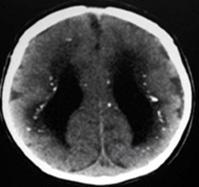

Toxoplasmosis congénita

Es causada por Toxoplasma gondii, quien es un protozoario intracelular del tipo Esporozoo (antiguamente llamados Apicomplexa), la infección en el feto ocurre a través de la transmisión de taquizoitos que atraviesan la placenta después de una infección materna primaria durante el embarazo, si la infección materna primaria ocurre a mayor edad gestacional mayor es el riesgo de infección (ENARM 2010-A), sin tratamiento la mayoría de infectados al principio del embarazo mueren intraútero o en el periodo neonatal o desarrollan severas secuelas neurológicas y oftalmológicas. La presentación clásica de la infección es la tétrada de Sabin, también llamada como las 4C (ENARM 2011-A, ENARM 2013-B) (calcificaciones intracraneales, hidrocefalia, corioretinitis y convulsiones), pero la gran mayoría cursa asintomática.

La sospecha diagnóstica se puede hacer en RN de madre que tuvo infección primaria en la gestación, RN de mujeres que están inmunosuprimidas y tienen evidencia serológica, RN con hallazgos compatibles, RN con pruebas de detección positiva para IgM de toxoplasma (en lugares donde se realiza). El diagnóstico se basa en la evaluación clínica, imágenes y pruebas de laboratorio. La confirmación se basa en la presencia de IgM o IgA especifica de toxoplasma o la detección molecular de ADN de T. gondii en LCR. Para el tratamiento se recomienda antiparasitarios en el siguiente régimen: pirimetamina 2mg/Kg (max 50mg/dosis) c/24h por 2 días, luego 1mg/Kg (max 25mg/dosis) c/24h por 6 meses, luego 1mg/Kg (max 25mg/dosis) 3 veces/ semana hasta el año; más sulfadiacina 100mg/Kg/día c/12h por 1 año; más ácido folínico 10mg 3 veces/semana durante y hasta 1 semana después de la terapia con pirimetamina; se podría asociar corticoide tipo prednisona 0.5mg c/12h si la proteínas en LCR es >1g/dl o cuando hay corioretinitis activa que amenaza la visión; para alergia a sulfadiacina puede ser sustituida por Clindamicina 20-30mg/Kg/día c/6h.